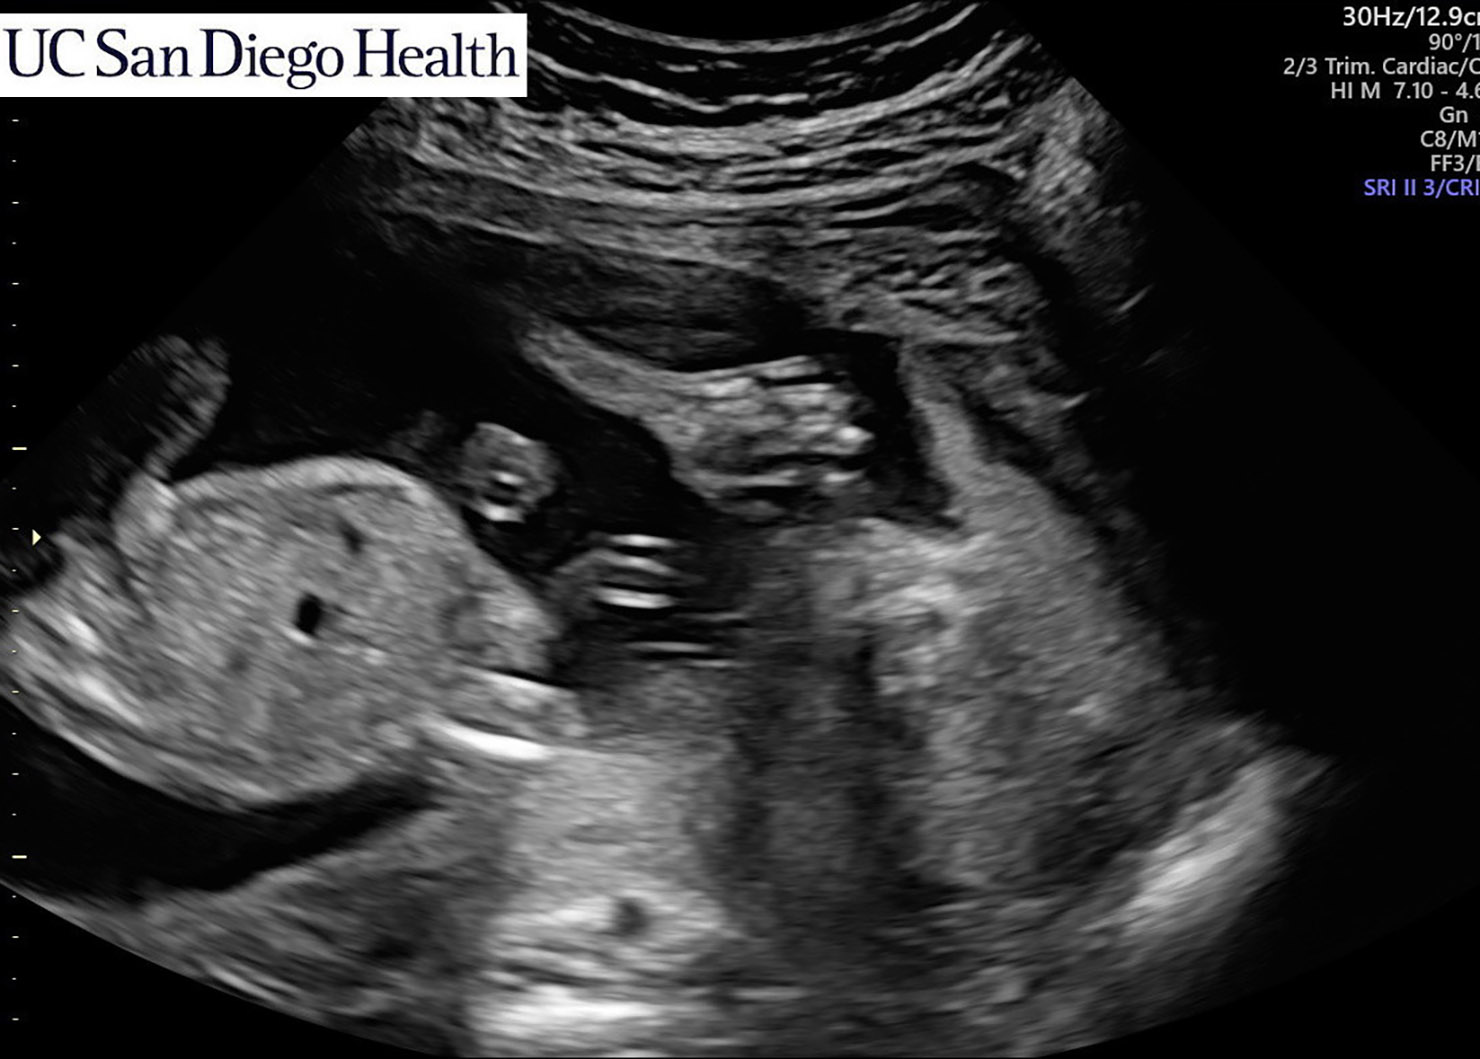

Anatomy Scan

You will have a mid-pregnancy ultrasound (often called the anatomy scan) between 18-20 weeks.

I had mine at 19 weeks.

This ultrasound provides information about your baby’s health and well-being, including size and growth, the position of the placenta, the baby’s heart rate, the amount of amniotic fluid, and potentially the sex of the baby, etc.

We found out our baby was in the 98% percentile for size at this appointment (aka a giant baby), so a follow-up anatomy scan was scheduled for Week 30 in my third trimester to assess their growth.